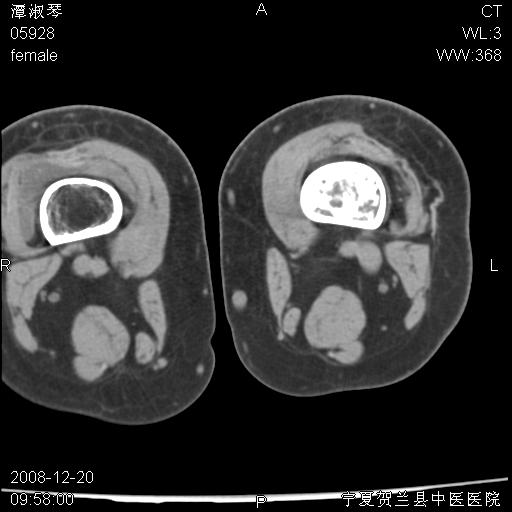

标题: CT17526:请各位看看是啥? [打印本页]

标题: CT17526:请各位看看是啥?

内生软骨瘤?骨梗死?

考虑内生软骨瘤可能性大

考虑-----骨梗死+退变

支持骨梗死,退行性骨关节病,膝关节积液.

考虑骨梗死可能性大

支持骨纤或内生软骨瘤或骨梗死,退行性骨关节病,膝关节积液.

骨梗死可能性大

左股骨下段骨梗死。双膝退变。

支持:内生软骨瘤或骨梗死!另:退行性骨关节病,膝关节积液。

左胫骨下端松质骨及髓腔内可见点片状高密度灶,骨皮质无明显膨胀及变薄。病变范围较长。支持骨梗死,退行性骨关节病,膝关节积液